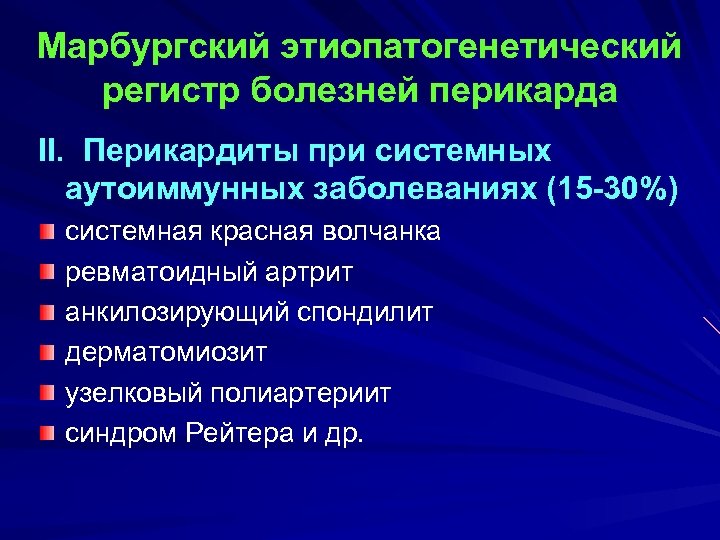

Марбургский этиопатогенетический регистр болезней перикарда II. Перикардиты при системных аутоиммунных заболеваниях (15 -30%) системная красная волчанка ревматоидный артрит анкилозирующий спондилит дерматомиозит узелковый полиартериит синдром Рейтера и др.